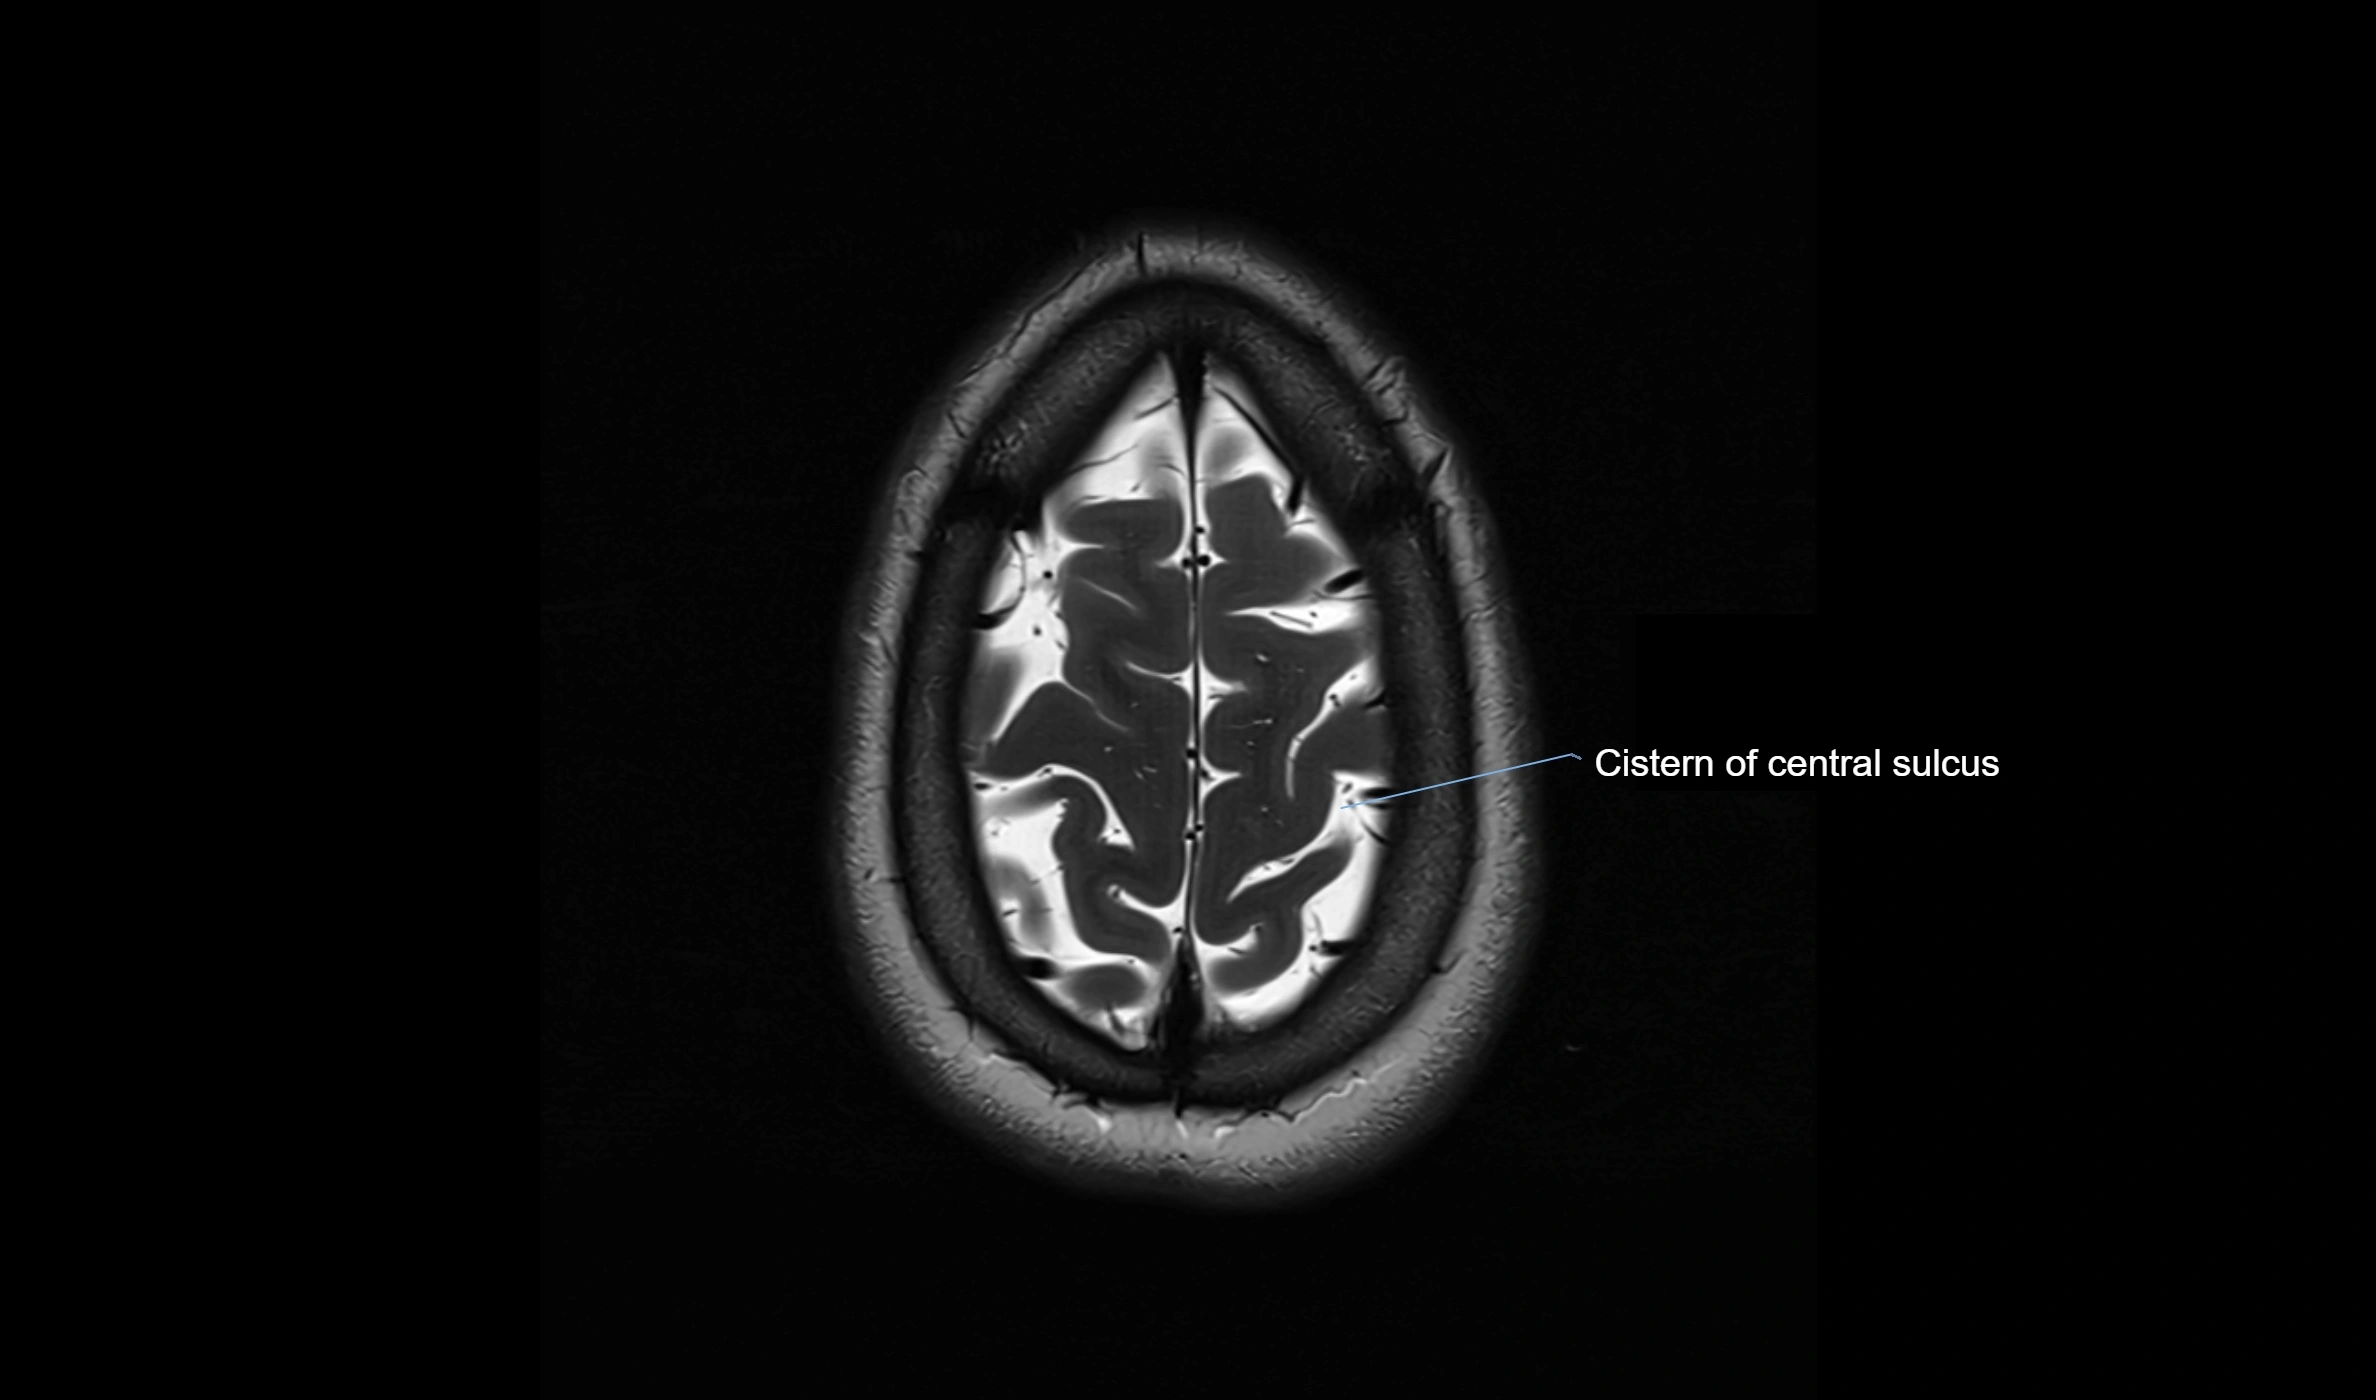

MRI images

image